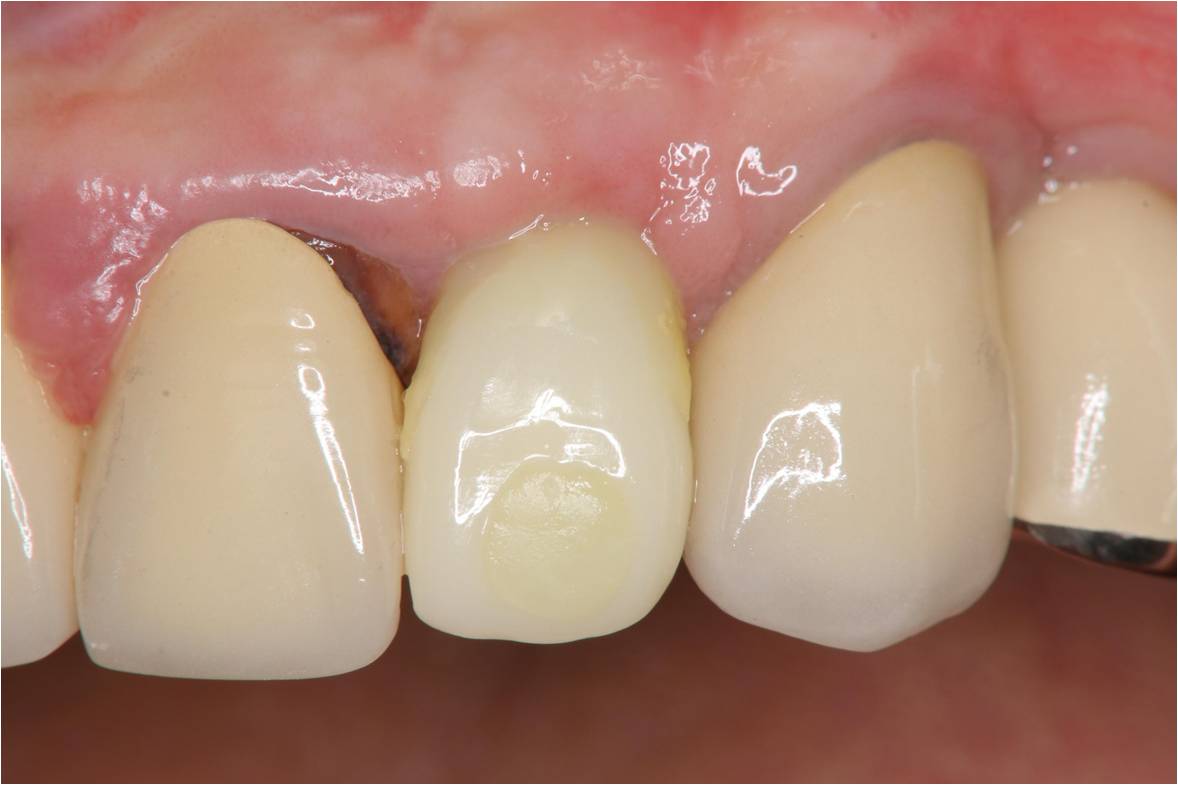

治療後口內照

術前、術後比較